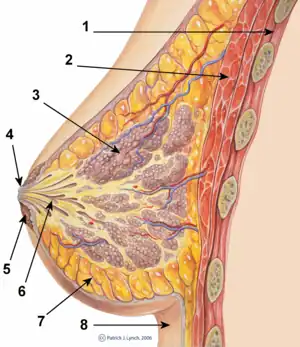

The breasts are apocrine glands which produce milk for the feeding of infant children,[19]

A person with breast implants is usually able to breastfeed an infant; yet implants can cause functional breastfeeding difficulties, especially with mammoplasty procedures that involve cutting around the areola, and implant placement directly beneath the breast, which tend to cause greater breast-feeding difficulties. Patients are advised to select a procedure which causes the least damage to the lactiferous ducts and the nerves of the nipple-areola complex (NAC).[22][23][24]

Functional breastfeeding difficulties arise if the surgeon cuts the milk ducts or the major nerves innervating the breast, or if the milk glands are otherwise damaged. Some surgical approaches, including IMF (inframammary fold), TABA (trans-axillary breast augmentation), and TUBA (trans-umbilical breast augmentation), avoid the tissue of the nipple-areola complex; if the person is concerned about possible breast-feeding difficulties, the periareolar incisions can sometimes be made so as to reduce damage to the milk ducts and to the nerves of the NAC. The milk glands are affected most by subglandular implants (under the gland), and by large-sized breast implants, which pinch the lactiferous ducts and impede milk flow. Small-sized breast implants, and submuscular implantation, cause fewer breast function problems; however, some women have managed to successfully breastfeed after undergoing periareolar incisions and subglandular emplacement.[24]